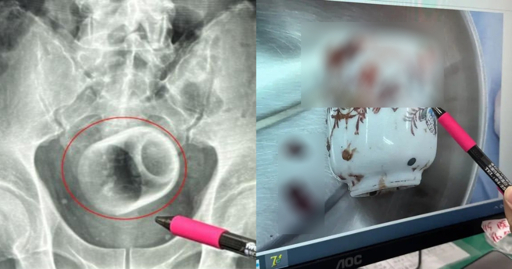

Things sometimes don’t come out due to shape or they lodge at a weird angle. This increases risk of bowel or rectal perforation as the body tries to push against an obstruction. Think opening a door but a desk is up against it. The cup can also break so now you’ll have ouchie shards that can cut the bowel and create perforations or spill stool into the abdomen. Oh, and cause bleeding.